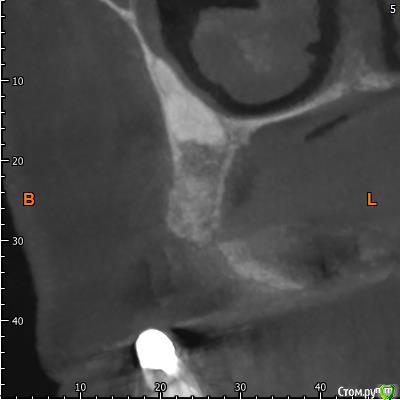

Павел7809 Опубликовано 9 апреля, 2018 Поделиться Опубликовано 9 апреля, 2018 Собственно ситуация такая. Предстоит каким то образом удалить ретенированный клык. Находится в небе, да и еще кривым апексом который торчит в носу. Полгода назад этому же пациенту почти такой же клык я удалил, но там как то все проще было по топографии. Собственно , господа, как и чем? Возможны ли какие то кровотечения носовые и тд. Кто сталкивался? Может как то распилить его со стороны щеки пополам и вытащить.. Ссылка на комментарий

Павел7809 Опубликовано 9 апреля, 2018 Автор Поделиться Опубликовано 9 апреля, 2018 Может так получше. Орто нет... Ссылка на комментарий

Павел7809 Опубликовано 9 апреля, 2018 Автор Поделиться Опубликовано 9 апреля, 2018 Так все тоже самое:Анестезия.Разрез.Декоронация.Удаление корня.Кюретаж.Швы.В нос провалитесь - плохо, но не страшно, будет кровать, тампонада носового хода.Я ведь правильно понимаю - сначала надо будет отрезать крючек со стороны щеки, сделав к нему окошко на уровне апексов 6 ки а потом удалить все остальное через небный доступ? Ссылка на комментарий

Борис80 Опубликовано 10 апреля, 2018 Поделиться Опубликовано 10 апреля, 2018 я бы вестибулярно делал, окно в области коронковой части, чуть апикальнее может, коронку отпилил, корень вывихнул Ссылка на комментарий